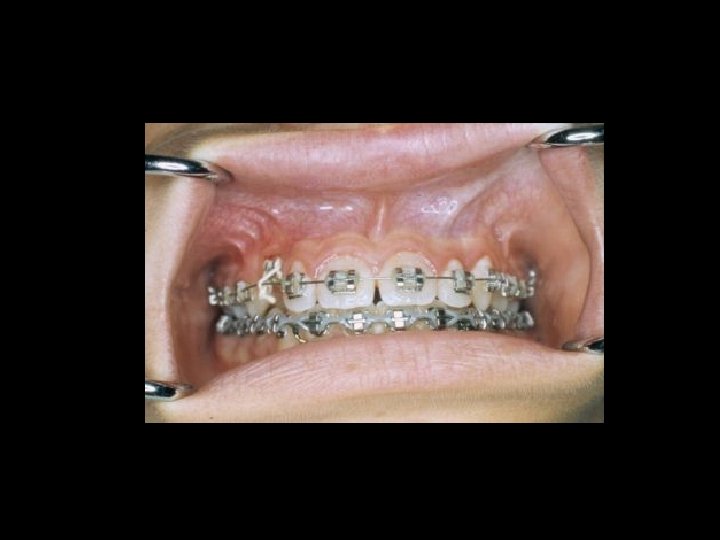

Il contenzioso PRINCIPALI AMBITI Ø Ø Ø La diagnosi La chirurgia orale La terapia conservativa Il trattamento delle anomalie dento-scheletriche La riabilitazione protesica

Responsabilità Ø Ø Ø Ø Garanzia di mezzi Garanzia di risultato Trattamento di soggetti in crescita Trattamento di soggetti al termine della crescita Comportamenti del paziente Risultato e recidiva Danni iatrogeni